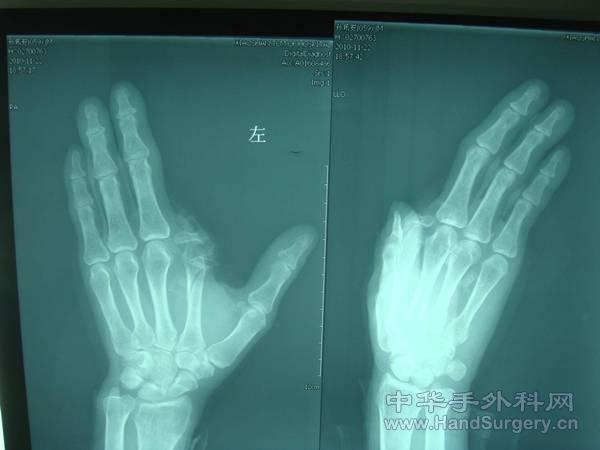

萧山区中医院11月份侯桥的再植及皮瓣作品

这是在新环境里,第一个月的手术资料,还没有完成随访!

图17、18至23、24,大家看看,讨论讨论。

同意楼上的!这个再植有意义吗?

这个病例再植没有意义!我把片子放在网上是想给大家看看,这个病人在自己6岁的时候食指生疮,指体的近、中节已经陈旧缺如,我给他做了废弃指皮瓣,当然最好是从第二掌骨去除指骨,但是这个病例我并没有谈下来。这个病人的指固有动脉在末节指端部,我接了两侧,都很纤细,接通后,近端皮瓣是慢慢渗红的,打算三个月后整形。谢谢,也希望听取您的意见!

17·18·23·24没必要,弄巧成拙